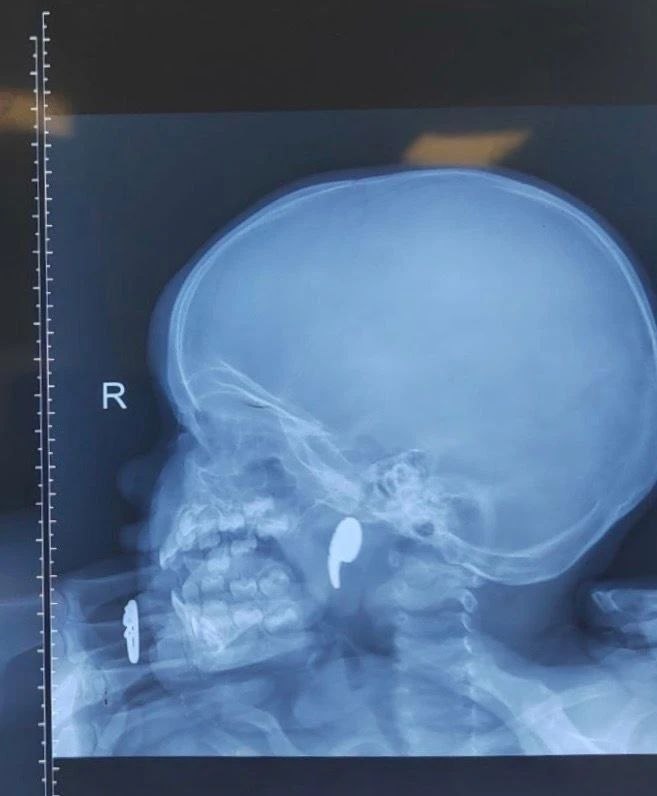

Мама сказала, что девочка играла с магнитом в форме запятой и подавилась им.

Магнит сместился в носоглотку.